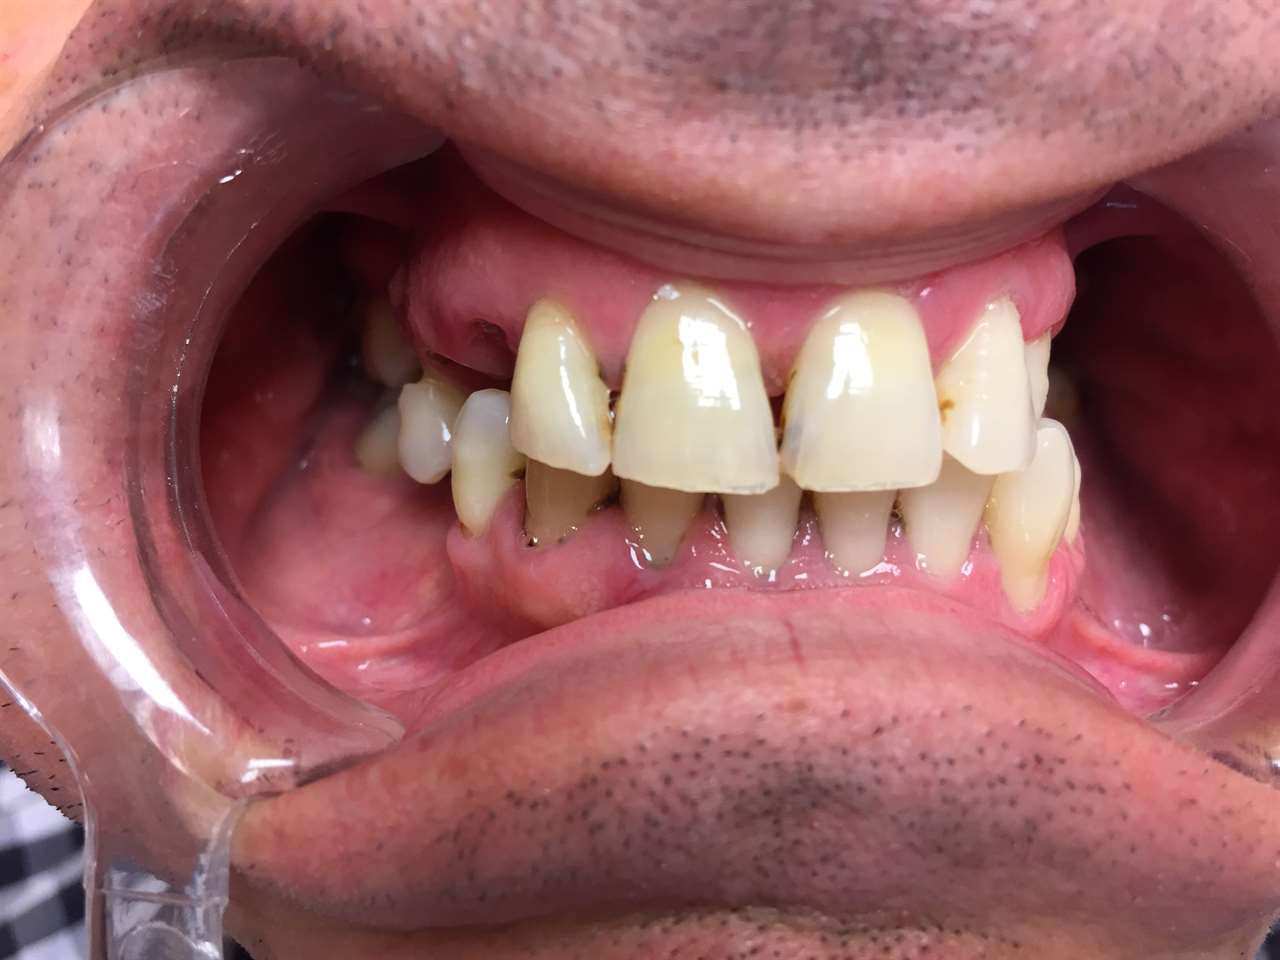

Alsó állcsont teljes rehabilitációja 72 óra alatt, azonnal terhelhető implantátumokkal súlyos paradontitisben szenvedő dohányzó páciens esetében. Az alsó állcsont fogai mind mozogtak az előrehaladott fogágypusztulás miatt.

A fogakat eltávolítottuk, a gyulladt, fertőzött csontot kitakarítottuk, kifertőtlenítettük, majd azonnal implantáltunk.

Svájci, IHDE márkájú, azonnal terhelhető implantátumokat helyzetünk be, és ezekre harmadnapra rögzített, hosszútávú, fémvázas, esztétikus műanyaggal leplezett hidat ragasztottunk be.

Ezt az ideiglenes hidat a sebek gyógyulása miatt használjuk, de tartóssága miatt véglegesként is használható. A legtöbb esetben, ahogy itt is, 6 hónap múlva porcelán hídra cseréljük, a teljes gyógyulás után.